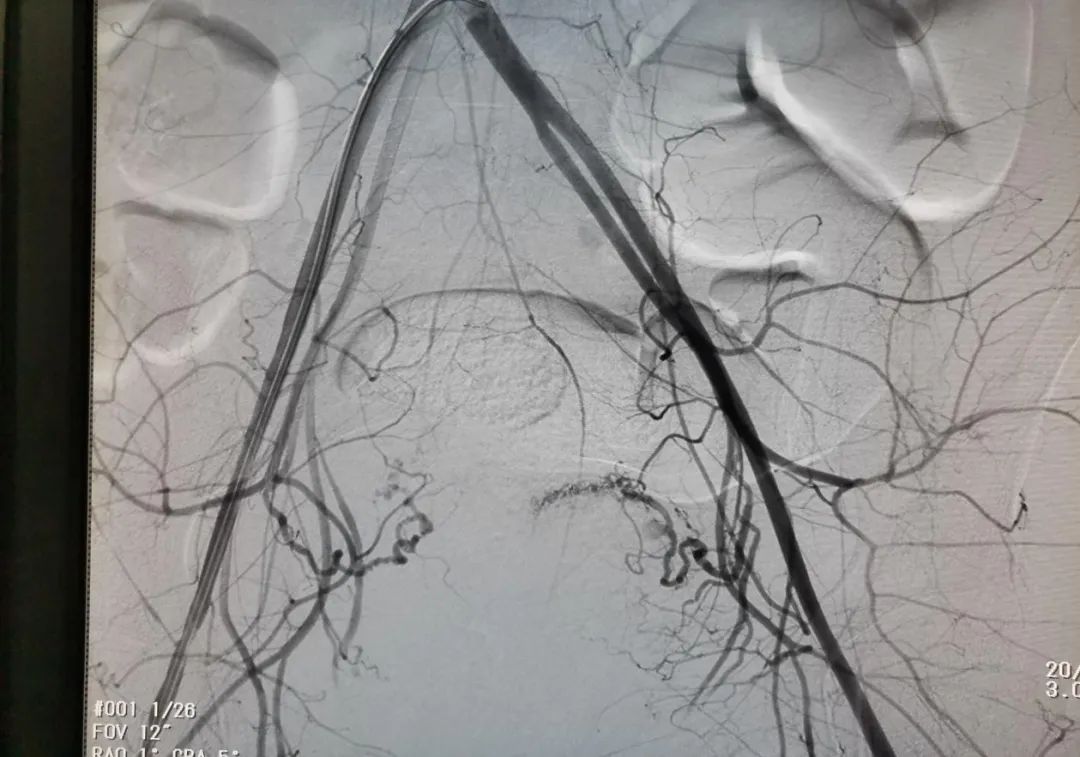

千钧一发之际,医院组织紧急多学科会诊讨论,确认患者病情允许进行血管介入手术,由血管介入科张世杰主任主刀、产科及妇科主任到场保驾护航,在局部麻醉下行右侧股动脉穿刺造影,见双侧子宫动脉活动性出血,如图1:

1子宫动脉栓塞术前